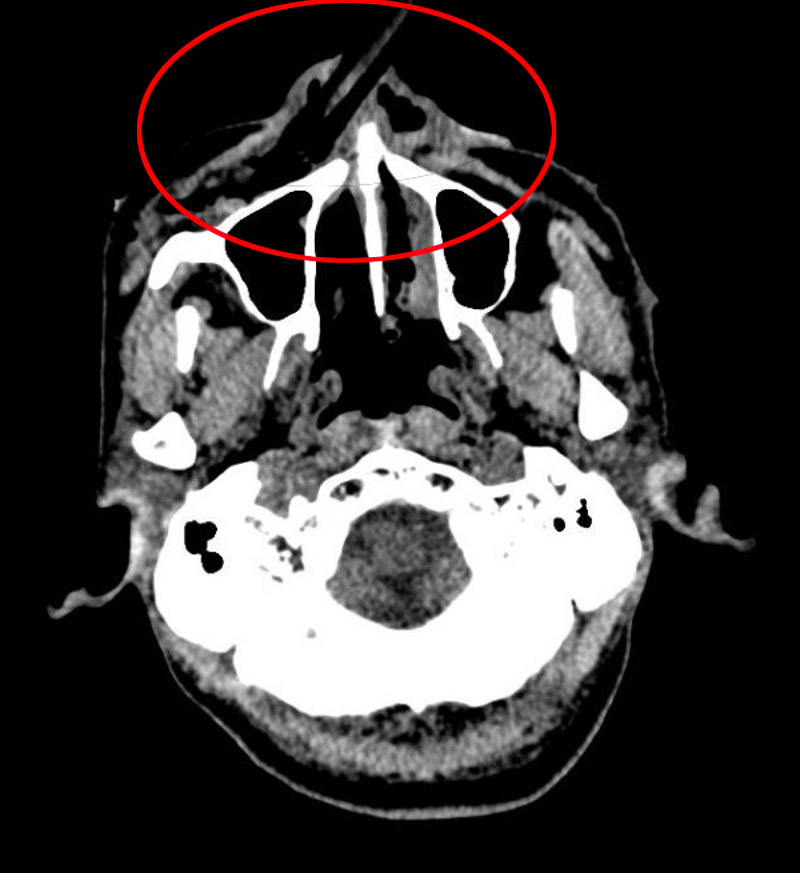

术中发现,竹棍由鼻尖处穿通鼻中隔插入鼻腔,贯穿鼻底黏膜,直达上颌窦前壁。口腔科主任宋勇博士小心翼翼地将竹棍拔出,此时,仍有大量竹棍碎屑残留在鼻腔内。由于竹棍在进入鼻腔后发生了折断,很多碎屑插入软组织,伤口深、视野差,清理难度大。如果异物清除不干净,会在创口内持续发炎,导致二次手术。